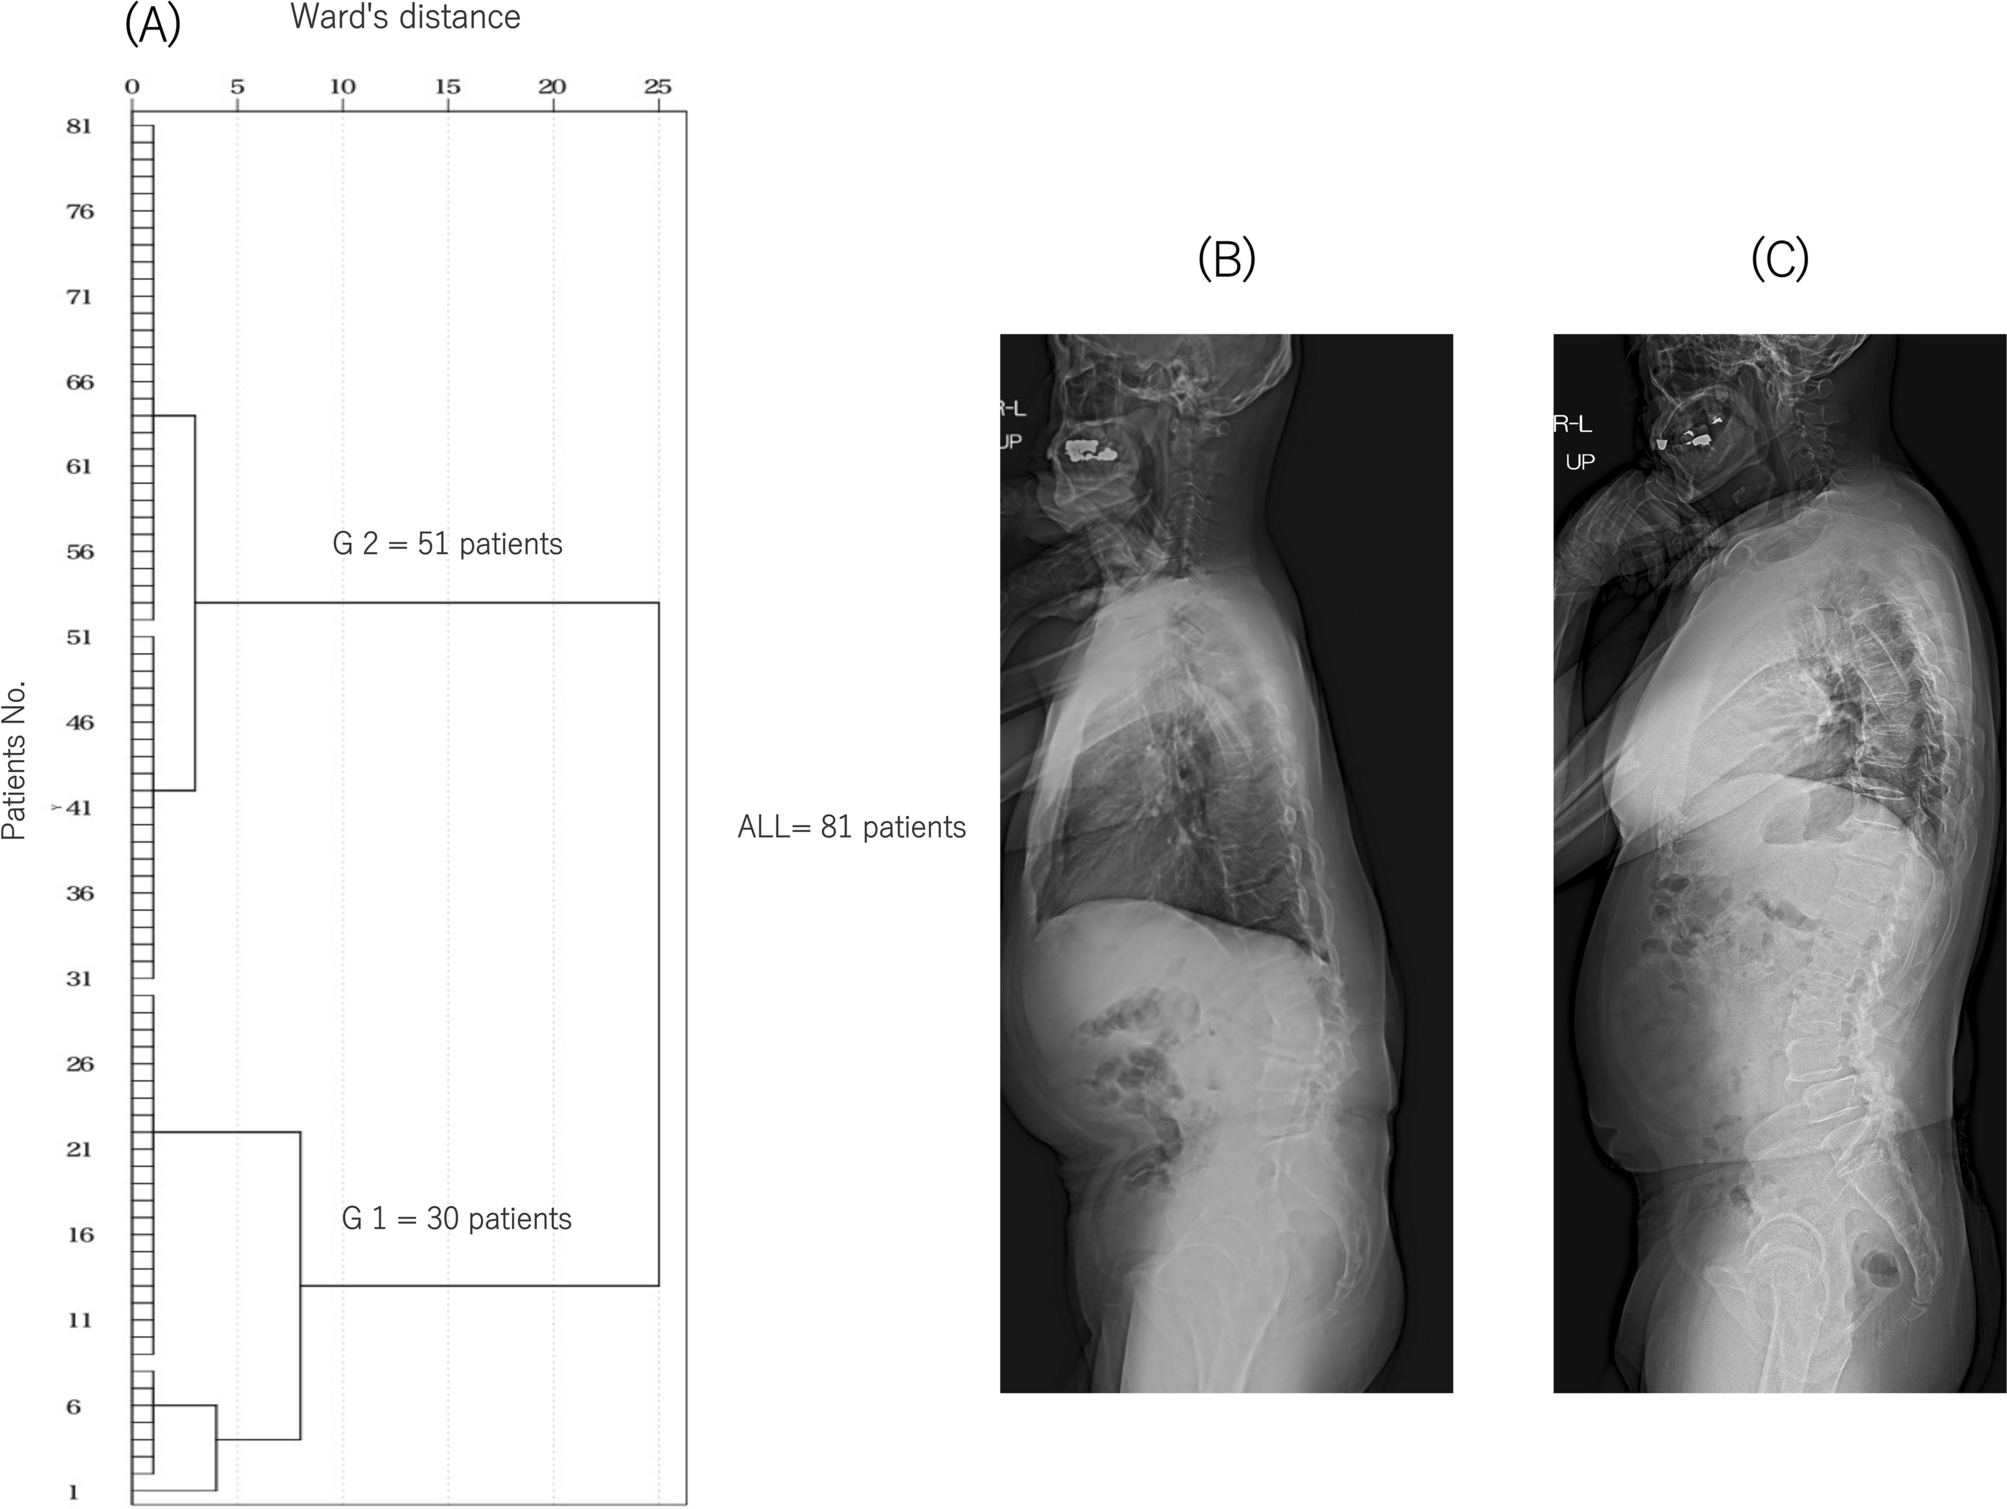

Dendrograms of the hierarchical classification of patients who received LLIF surgery (n = 81). (A) The numbers of patients in each cluster at different Ward’s distances are shown. The patients were classified into groups 1 (n = 30) and 2 (n = 51) from the cluster analysis. Standing full-length X-ray lateral views of typical cases in groups 1 (B) and 2 (C).